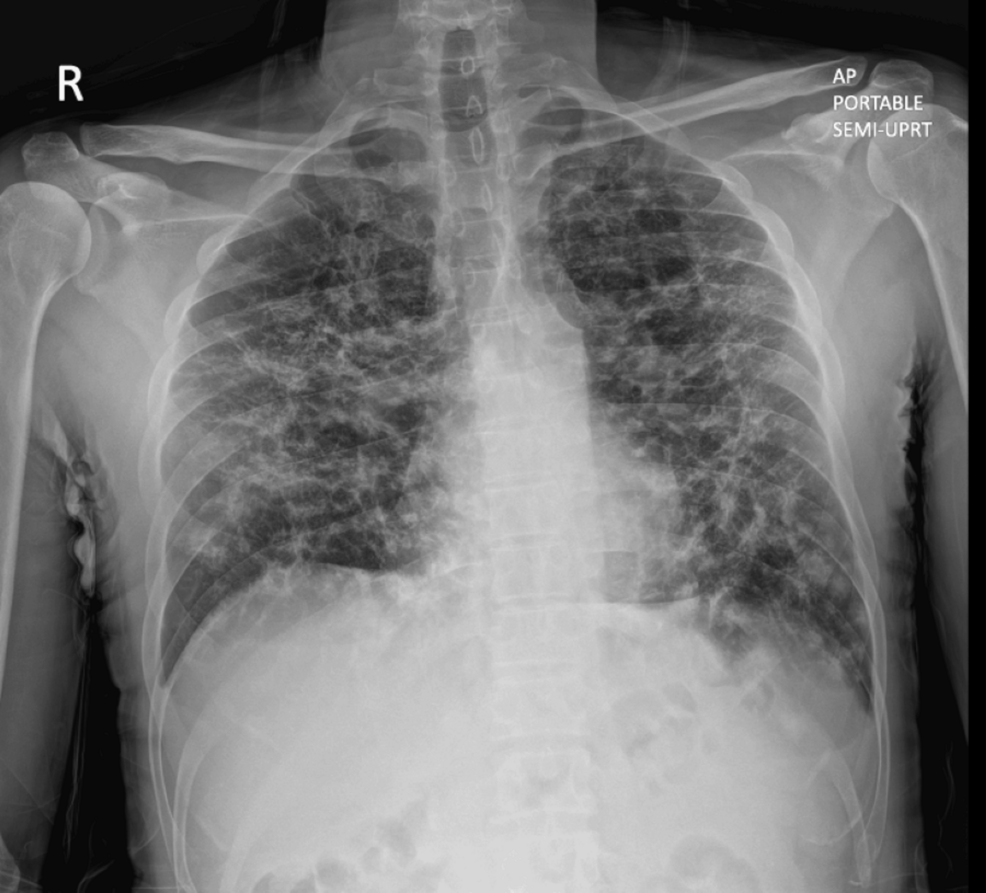

La sarcoidosis es una enfermedad inflamatoria sistémica que puede afectar a múltiples órganos. Si bien a menudo se diagnostica en los pulmones, también puede presentarse en el abdomen, afectando al peritoneo y al hígado. En este caso, la sarcoidosis no fue la razón inicial de la cirugía, sino que se descubrió accidentalmente durante la exploración laparoscópica para la extirpación del apéndice.